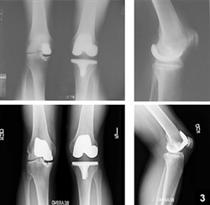

استئوآرتريت قابل پيشگيري است

استئو آرتريت يا آرتروز يکي از رايج ترين بيماري ها در بين بزرگسالان است به طوري که آمارها حاکي از آنند که حدود 8 ميليون نفر از افراد در انگلستان، دچار آرتريت هستند. ابتلا به اين بيماري در بين زنان بيش از مردان است و متاسفانه شيوع اين عارضه در کشور ايران نيز قابل توجه است..

بيماري سبب ايجاد درد و ناتواني ..در سنين ميان سالي و کهنسالي مي شود